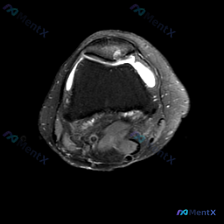

主诉软骨异常但单张T1像未见明显异常?这个膝关节影像病例值得捋捋思路

这是一份膝关节单张正中矢状位T1加权MRI图像的分析需求,核心问题是:观察到了软骨异常,需要进一步评估。

- 序列与解剖:图像为膝关节正中矢状位T1加权序列,图像质量好,结构清晰,可见髌骨、髌腱、前后交叉韧带、股骨髁、胫骨平台

- 骨骼:股骨远端、胫骨近端、髌骨骨髓信号均匀,未见局灶性异常信号,排除明显骨髓水肿或占位

- 软骨与关节面:股骨滑车及胫骨平台关节软骨下骨皮质连续,未见明显骨缺损或剥脱性改变,髌股关节对合良好

- 韧带肌腱:前后交叉韧带连续性完好,走行信号正常;髌腱、股四头肌腱形态信号正常,未见撕裂

- 半月板:前后角形态信号正常,未见异常高信号,排除明显撕裂

- 其他:关节腔内可见少量低信号液体影(髌上囊及关节间隙),腘窝区未见异常占位或囊肿